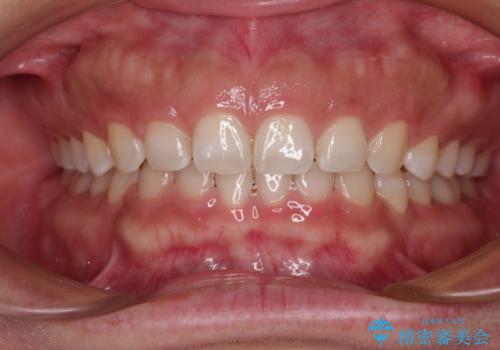

- 出っ歯と口の閉じにくさ、デコボコを気にして来院された患者様です。

口元の突出感を改善するため、上下左右第一小臼歯4本の抜歯を行い、ワイヤー装置による矯正治療を行うこととしました。

舌の突出癖により上下前歯は非接触であり、非常に前方に飛び出している状態でした。

舌のトレーニングをしっかりと行っていただき、口の閉じやすい歯並びに仕上げることができました。